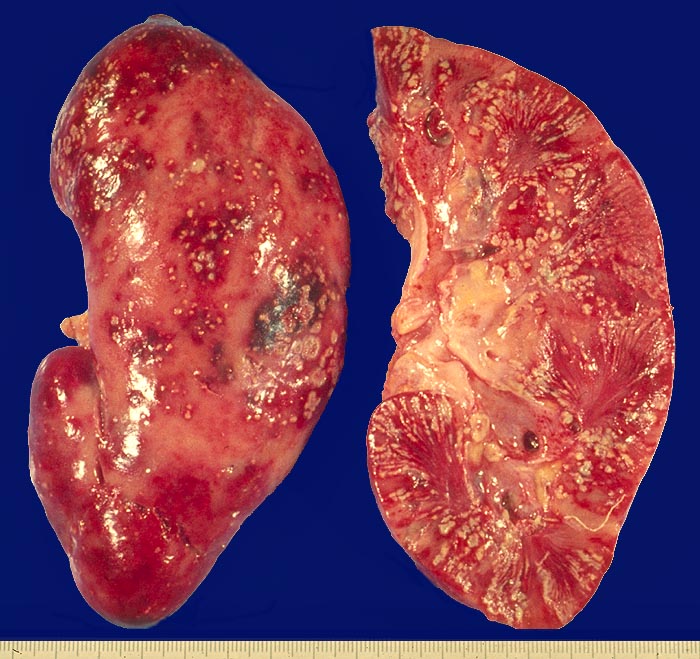

Symptomatik:

Die Patienten haben Fieber über 38°C, Flankenschmerzen, klopfschmerzhafte Nierenlager, Übelkeit, Erbrechen und ev. einen paralytischen Ileus. Pollakisurie und Dysurie können fehlen.

Komplikationen:

Als gefürchtete Komplikation kann sich eine Urosepsis (und ev. septischer Schock) meist mit gram negativen Keimen entwickeln. Besonders gefährdet sind Patienten mit Harnwegsobstruktion, Dauerkatheter, Zystennieren, Schwangerschaft, Diabetes mellitus und Immunsuppression.